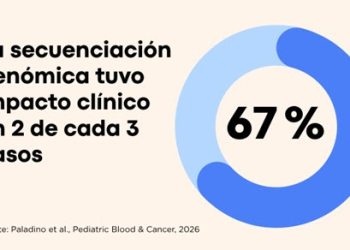

Leer másArgentina logra aplicar medicina de precisión en cáncer infantil y mejora el diagnóstico en dos de cada tres casos

Un proyecto desarrollado por investigadores y médicos de instituciones argentinas y de la región demuestra que...